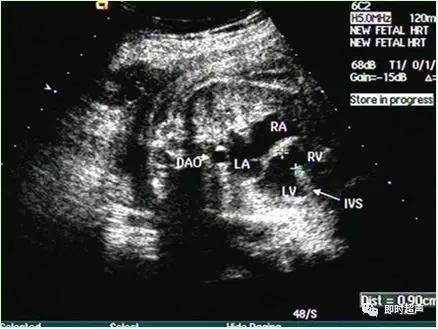

十一、室间隔缺损(VSD)

超声特点:常见的一种CHD,占其中20-25%可与其他心内畸形并存。

超声诊断VSD意义评估:①单纯VSD一般临床预后好,建议行染色体核型分析合并染色体异常的发生率18%。②VSD与其他心内或心外畸形并存预后多不良,可选择终妊妊娠。③不要因单纯VSD改变分娩方式和时间,出生后小缺损可自然闭合,大则及早手术修补 。

十二、房间隔缺损ASD房间隔缺损(ASD)

房间隔缺损(ASD)超声特点

四腔心断面上超声未发现卵圆孔瓣漂入左房,卵圆孔直径>8mm,应怀疑 存在ASD的可能性。

超声ASD处理原则同VSD。